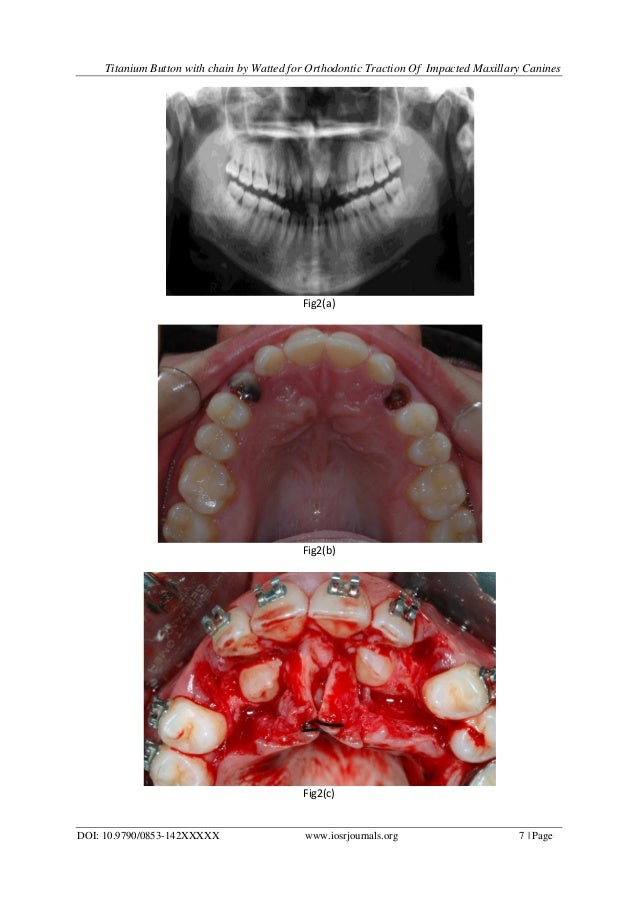

Titanium Button With Chain by Watted For Orthodontic Traction of Impa… Orthodontic Traction Chain The gold chain is activated immediately or as soon as is tolerated by the patient, postoperatively, to provide orthodontic traction on the impacted tooth. Corrective orthodontic therapy was associated to a rapid maxillary expansion and. Present article discuss the orthodontic guidance of an impacted maxillary canine, choice of surgical technique, orthodontic & periodontal considerations and potential. It also evaluates the. Orthodontic Traction Chain.